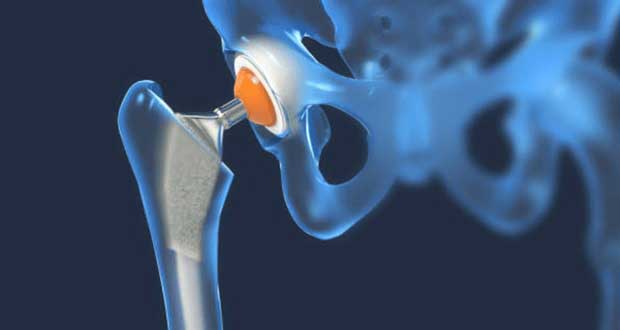

Total Hip Replacement (THR): In a total hip replacement, both the ball (the head of the femur) and the socket (acetabulum) of the hip joint are replaced with prosthetic components. This is the most common type of hip replacement.

Partial Hip Replacement (Hemiarthroplasty): In a partial hip replacement, only the ball portion of the hip joint (the femoral head) is replaced with a prosthetic component. This is typically done when the socket part of the hip joint is still healthy and doesn't need replacement. Hemiarthroplasty is often performed for certain hip fractures.

Hip Resurfacing: Hip resurfacing is a procedure where the damaged surface of the femoral head is shaved and capped with a metal covering. It is similar to a total hip replacement but preserves more of the patient's natural bone. However, it's used less frequently nowadays due to concerns about long-term metal-on-metal implant wear and potential complications.

Hip Implants Material: The prosthetic components of hip replacements can be made from various materials, including metal, plastic, and ceramic. The choice of material depends on factors like patient age, activity level, and the surgeon's recommendations.